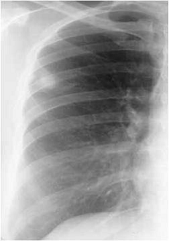

Когда опухоль прилежит к междолевой щели, можно видеть легкое втяжение утолщенной плевры (симптом паруса).

Контуры сравнительно небольших периферических опухолей в большинстве случаев нечеткие. Это свидетельствует о том, что на ранних стадиях развития раковый процесс имеет склонность к инфильтративному росту. Позднее, когда размеры опухоли превышают 2,5 см диаметром, ее контуры становятся бугристыми, но более четкими.

На более поздних этапах развития появляется дорожка ракового лимфангита, связывающая опухоль с корнем. Различают два вида дорожек: одна из них - в виде неоднородной тяжистости за счет периобронхиальной и периваскулярной опухолевой инфильтрации, вторая - однородная, широкая, связанная с цепочкой метастатически измененных лимфоузлов или с ростом самой опухоли. В корне появляются увеличенные лимфоузлы. В этих случаях говорят о фазе биполярности. Распространение опухолевого процесса на крупный бронх вызывает его обструкцию, присоединяется ателектаз - происходит так называемая централизация периферического рака. Однако симптом "дорожки к корню" для постановки диагноза периферического рака самостоятельного значения не имеет, т.к. может встречаться и при других заболеваниях (туберкулезе, хронической пневмонии). Отмечается, что при раке (в отличие от туберкулеза) в дорожке редко виден дренирующий бронх.

Таким образом, периферический рак на разных стадиях эволюции имеет разную рентгенологическую картину, и, следовательно, дифференциально-диагностический ряд в каждом случае иной. На ранних стадиях развития периферический рак чаще всего похож на очаг воспаления или пневмосклероза и гораздо реже напоминает доброкачественную опухоль или кисту.